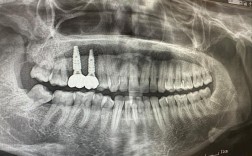

| 愈合期管理 | 3-6个月骨结合期内佩戴过渡义齿维持咬合关系;每月复查X光片观察骨生长情况 | 禁止咀嚼硬物防止种植体松动 |